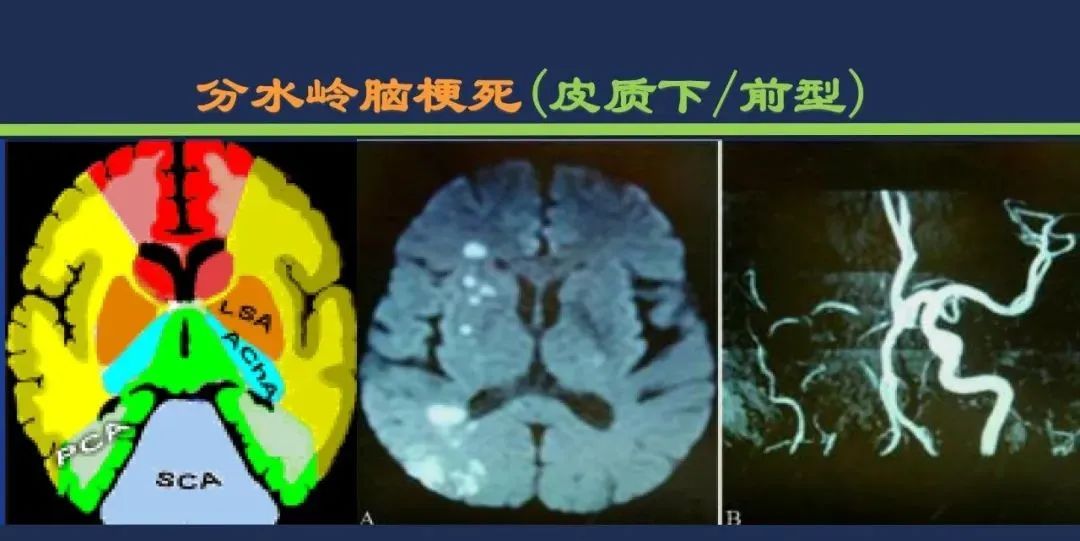

分水岭梗死皮质前型+皮质后型+后上型皮质下前型+皮质下后型+皮质下上型+皮质下外型+皮质下下型